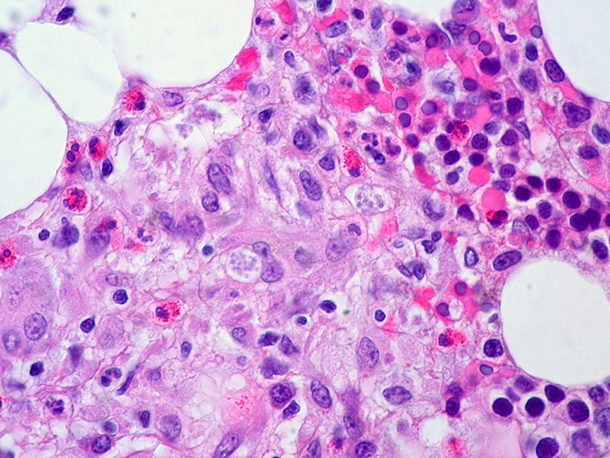

Fungal infections take about a million lives worldwide every year. (Photo: Ed Uthman, Flickr CC BY 2.0)

DYKSTRA: Yeah but not always. We’ve been increasing the use of fungicides on crops, and researchers have identified that as a factor in the potential rise of drug resistance. Athlete’s foot fungus can make your toes itch, but an aspergillus infection could go straight for your nervous or immune systems. Some estimates tell us that fungal infections may already claim a million lives per year worldwide, and they also threaten an iconic food source.